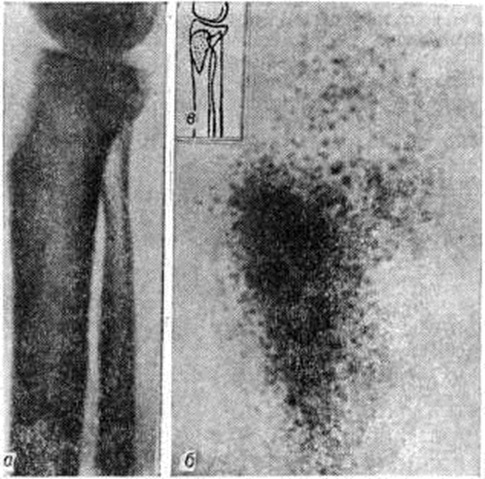

При несвоевременно начатом или неэффективном лечении в конце 3-й — начале 4-й недель после заболевания острым Остеомиелит на рентгенограммах вокруг деструктивных очагов на фоне остеопороза обнаруживается картина диффузного и распространённого эностального остеосклероза (рисунок 13), который резко отличается, например, от узкой зоны остеосклероза при туберкулёзном остите. Остеосклероз распространяется по длиннику кости, интенсивность его нарастает; на фоне склероза выявляются новые очаги деструкции. Распространённый остеосклероз при Остеомиелит характеризует переход процесса в хронический. Вследствие периостального и эностального костеобразования нарастает толщина и плотность поражённой кости.

Самые ранние рентгенологическое признаки огнестрельного и травматического хронических Остеомиелит появляются через 3— 4 недель после травмы. Первый прямой симптом его — остеопороз жизнеспособных отломков костей, который особенно отчётливо определяется, если имеются потерявшие связь с надкостницей и сосудами омертвевшие отломки. В то время как живая кость подвергается остеопоротической перестройке, в некротизированных участках этот процесс не происходит, они могут в неизменённом виде находиться в тканях годами, поддерживая воспаление. Выглядят некротизированные участки более плотными по сравнению с порозной, сохранившей жизнеспособность костью. Другим сравнительно ранним признаком воспаления в области отломков является разрушение их краёв, вследствие чего они теряют свою угловатость, резкую очерченность, контуры их становятся нечёткими. И, наконец, третий ранний признак Остеомиелит— появление периостальных наслоений (смотри полный свод знаний Периостит) вдоль концов отломков. Наслоения эти отделены от кости полоской просветления, обусловленной грануляционной тканью, разрастающейся между костью и отслаивающейся надкостницей. В дальнейшем эти концевые участки отломков, окружённые почти со всех сторон воспалительными грануляциями или гноем, в наибольшей степени подвержены секвестрации. Наряду с секвестрацией появляются все новые и новые очаги воспалительной деструкции в живых участках кости, вокруг которых на фоне нарастающего регионарного остеопороза развивается характерный для хронический Остеомиелит остеосклероз (рисунок 17).

Определённую роль, особенно в дифференциальной диагностике хронический Остеомиелит и опухоли кости, начинает играть радиол, метод исследования. Сцинтиграфия (смотри полный свод знаний) после введения изотопов (пирофосфата технеция или стронция) помогает установить первоначальные признаки воспалительного процесса и распространённость его в различных костях раньше, чем рентгенография (рисунок 18), однако мелкие секвестры и остеомиелитические очаги легче обнаружить с помощью рентгенологическое метода.